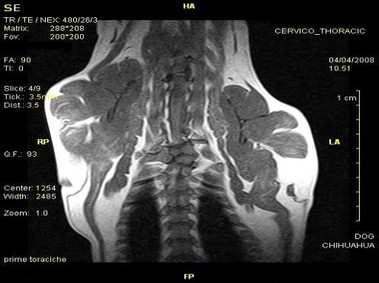

В настоящее время МРТ является наиболее предпочтительным методом визуализации любых мягких тканей, особенно для визуализации травм и патологий центральной нервной системы и суставов. Особенности Vet-MR позволяют использовать данный метод визуализации также в сфере ветеринарии.

Vet-MR специально разработана для визуализации небольших животных и является результатом внимания к деталям при разработке магнита, катушки и электронных компонентов, обеспечивая высокое качество экономически эффективной и простой в использовании МРТ в сфере ветеринарии.